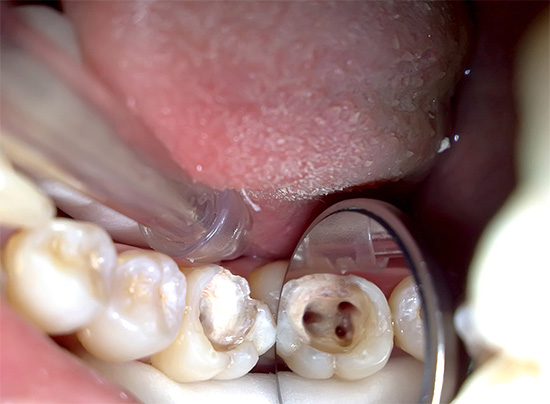

Foto di un dente con polmonite gangrenosa cronica: un'ombra grigia malsana è chiaramente visibile:

Quando si esamina un dente, la sua tinta grigia colpisce di solito in presenza di una cavità cariata che si estende in profondità nella bocca dei canali radicolari. Quando si sondano, si nota la presenza di una grande quantità di dentina ammorbidita cariata e la penetrazione profonda dall'estremità acuta della sonda nella bocca dei canali radicolari è spesso dolorosa, sebbene a volte si verifichi dolore quando viene uccisa una parte della polpa radicolare.